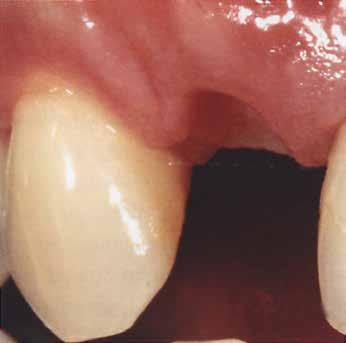

A 80 éves páciens 22-es fogának hiányát szerette volna megoldatni a rendelőben. Az implantációt költségessége miatt nem tudta vállalni. A 21-es fog már koronával volt ellátva, és kategórikusan elutasította ennek lengőtagos híddal való lecserélését, így egyértelmű volt a 23-as fogon való rögzítés szükségessége.

Az egyszárnyú ragasztott híd mellett döntöttünk (1. a kép)

Mivel a szemfogak általában nagyon közel vannak az antagonistához, kettes pótlására a szárnyat inkább a nagymetszőre szoktuk tervezni. Ehhez persze invazív preparációra van szükség – érintetlen fogak esetén ez lehetőleg kerülendő.

A bemutatott esetben azonban könnyen döntöttünk, mivel a szemfog disztális részén nagy tömés volt. A defektust bevontuk az eset megoldásába.

Végezetül részletfelvételek egy másik ragasztott hídról, amely hasonló módon készült, hat hónappal a behelyezés után (42–43. képek)

A hídtag enyhe mozgathatósága miatt az íny stimulálva volt. Ezzel a vérellátás további segítséget kapott, ami a lágyszövet kiváló adaptálódását hozta magával.